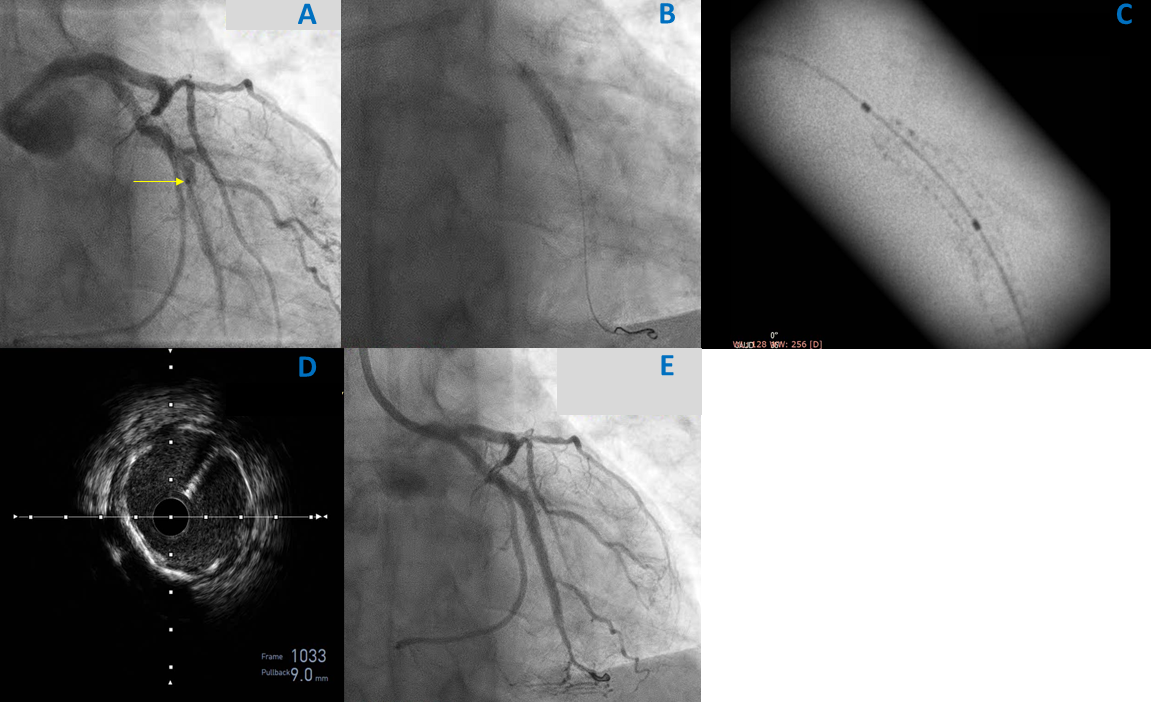

Coronary angiography showed a severely underexpanded stent in the OM1, confirmed by stent boost and caused by calcification (Figure 1A and B). Advancement of intravascular ultrasound (IVUS) through the stenosis was not feasible. Dilatations with noncompliant balloons failed to expand the previously implanted stent (Figure 1C). It was decided to proceed with ELCA (Philips). Although lasing with a 0.9-mm catheter under saline injection failed, subsequent lasing under contrast injection achieved lesion ablation (Figure 2A, Video 1, Video 2). A noncompliant balloon was then dilated symmetrically, allowing adequate stent expansion illustrated by stent boost and IVUS (Figure 2B-E).

ELCA uses ultraviolet energy (wavelength: 308 nm) delivered by a xenon-chlorine pulsed laser catheter with pulse frequency of 25 to 80 Hz and fluence of 30 to 80 mJ/mm2, leading to disruption and disintegration of the molecular bonds within the atherosclerotic plaque in a highly controlled manner through ablation rather than burning.1 Compared with atherectomy devices, it has the advantage that it can be advanced through a standard 0.014-inch guidewire and can modify the lesion without crossing it. Lasing with saline is in general safer and is preferred; however, activation with simultaneous contrast injection creates a powerful acoustic mechanical effect with the formation of multiple large-sized bubbles that can effectively debulk and soften calcium, leading to stent expansion in case the former technique fails.2-4